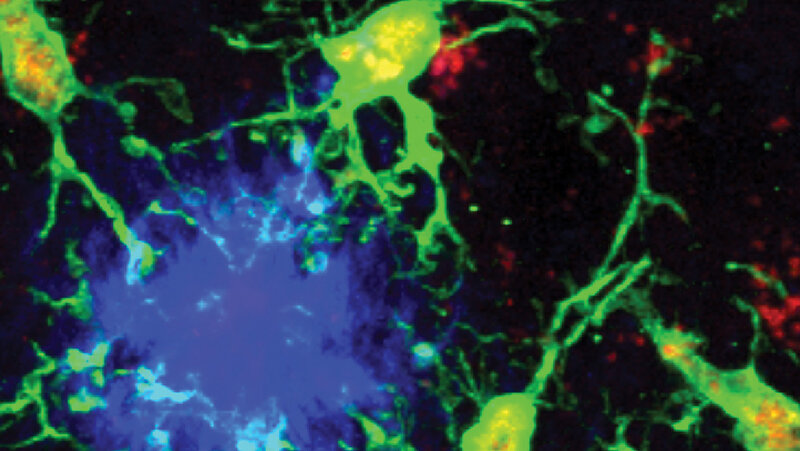

Alzheimer ist die häufigste Form einer Demenz-Erkrankung. Hierfür spielen auch die Immunabwehrzellen des Gehirns, die Mikroglia, eine wichtige Rolle. Sie wirken sowohl schützend als auch krankheitsfördernd und können dadurch den Verlauf der Alzheimererkrankung aktiv beeinflussen. Ein internationales Forschungsteam unter Beteiligung des Max-Planck-Instituts ür Biologie des Alterns aus Köln entdeckte die Gruppe der neuroprotektiven Mikroglia, die eine Möglichkeit für einen neuen Therapieansatz aufzeigen.

Anhand von Mausmodellen zu Alzheimer, menschlichen Zellen und menschlichem Hirngewebe konnten die Forschenden den Transkriptionsfaktor PU.1 als wichtigen Faktor identifizieren. Es zeigte sich, dass weniger PU.1 die Expression von Rezeptorproteinen des lymphoiden Immunsystems auf Mikroglia fördert. Denn trotz geringer Anzahl haben diese Mikroglia eine schützende Wirkung auf das Gehirn. Die kognitiven Funktionen von Mäusen und damit einhergehend auch das Überleben der Mäuse konnte besser erhalten werden.

Außerdem zeigte sich, dass die Entzündung und das Plaquewachstum verstärkt wurden, wenn man CD28 aus der Untergruppe der Mikroglia entfernte. CD28 hat demnach eine stark schützende Rolle. „Mikroglia sind nicht einfach nur zerstörerische Gegenspieler bei der Alzheimer-Krankheit – sie können zu Beschützern des Gehirns werden“, erläutert Anne Schaefer, leitende Autorin der Studie und Leiterin des Projekts. „Diese Erkenntnis erweitert unsere früheren Beobachtungen zur bemerkenswerten Plastizität der Mikroglia-Zustände und ihrer wichtigen Rolle bei verschiedenen Gehirnfunktionen. Sie unterstreicht auch die entscheidende Bedeutung der internationalen Zusammenarbeit für den wissenschaftlichen Fortschritt.“